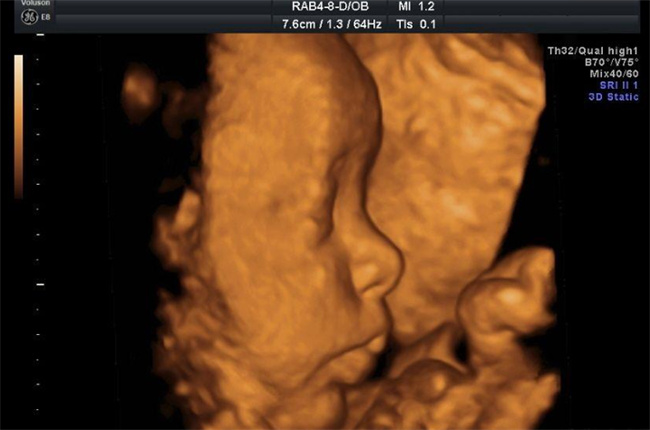

所谓三维彩超,是一种高级的成像技术,通过它,我们可以清晰地看到宝宝的每一个细节,仿佛宝宝就在眼前一样。相比传统的二维彩超,三维彩超不仅能够展现出更加真实的立体图像,还可以实时地观察胎儿的各种动态,让准妈妈们更加亲近自己的宝宝。在进行三维彩超检查时,医生会将探头放置在孕妇的腹部,通过高频声波,可以清晰地看到宝宝在子宫内的样子。与此同时,医生也可以从不同的角度观察宝宝的各个部位,比如头部、四肢等,从而全面了解胎儿的生长发育情况。

对于许多准爸妈来说,最期待的莫过于知道自己的宝宝是男孩还是女孩。在传统的二维彩超中,通常在孕16周末就可以通过观察宝宝的外生殖器来初步确定性别。然而,这种方法并不总是百分之百准确,有时候会存在误差。而在三维彩超中,由于可以从多个角度观察宝宝的性别特征,因此可以提高性别判断的准确性。不过需要注意的是,尽管三维彩超能够提供更多的信息,但最终的性别鉴定还是需要由专业医生进行判断。因为胎儿在不同的发育阶段,性别特征可能会有所不同,而且有时候宝宝的姿势也会影响到判断的准确性。